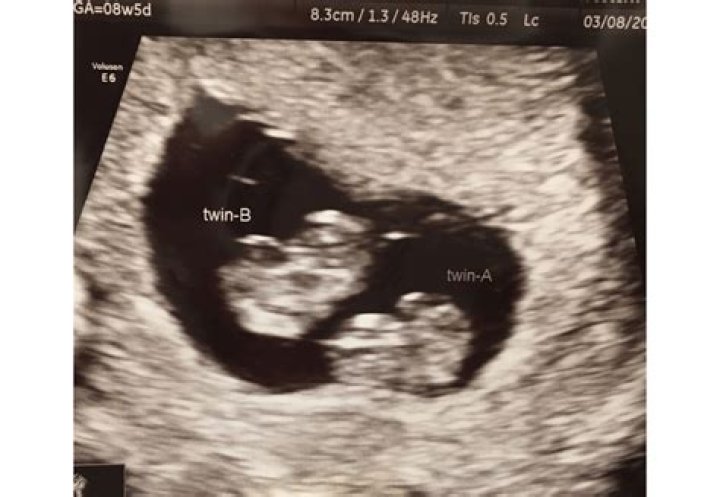

Can you tell if you are having twins at 8 weeks?

Ultrasound. Although the factors above may be signs of a twin pregnancy, the only sure way to know you're pregnant with more than one baby is through an ultrasound. Some doctors schedule an early ultrasound, around 6 to 10 weeks, to confirm the pregnancy or check for issues.

Can you miss a twin at 8 week ultrasound?

The baby's heartbeat can't usually be detected before about 7-8 weeks, but some scans are performed before this. If one of the tiny twins happens to be hidden behind the other when the scan is performed, then there might not be any clue that you're carrying more than one baby.

Can you see twins at 7 weeks?

If your twins are fraternal — meaning, two different eggs were fertilized — there will be a separate gestational sac for each baby. If you're estimating your pregnancy accurately, multiple sacs should be pretty visible on a transvaginal ultrasound at 7 weeks.